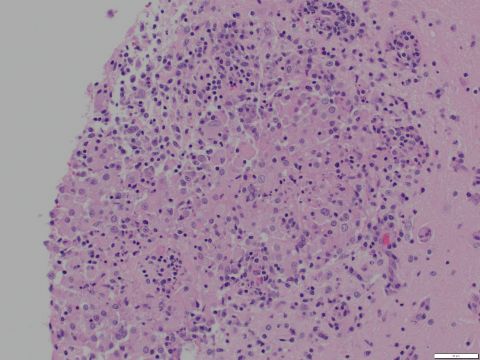

Species: Rabbit

Brain

Focal granulomatous and necrotizing encephalitis with intralesional gram positive microsporidian spores.

Cause of death was predator trauma. Unrelated to E. cuniculi infection which was incidental.